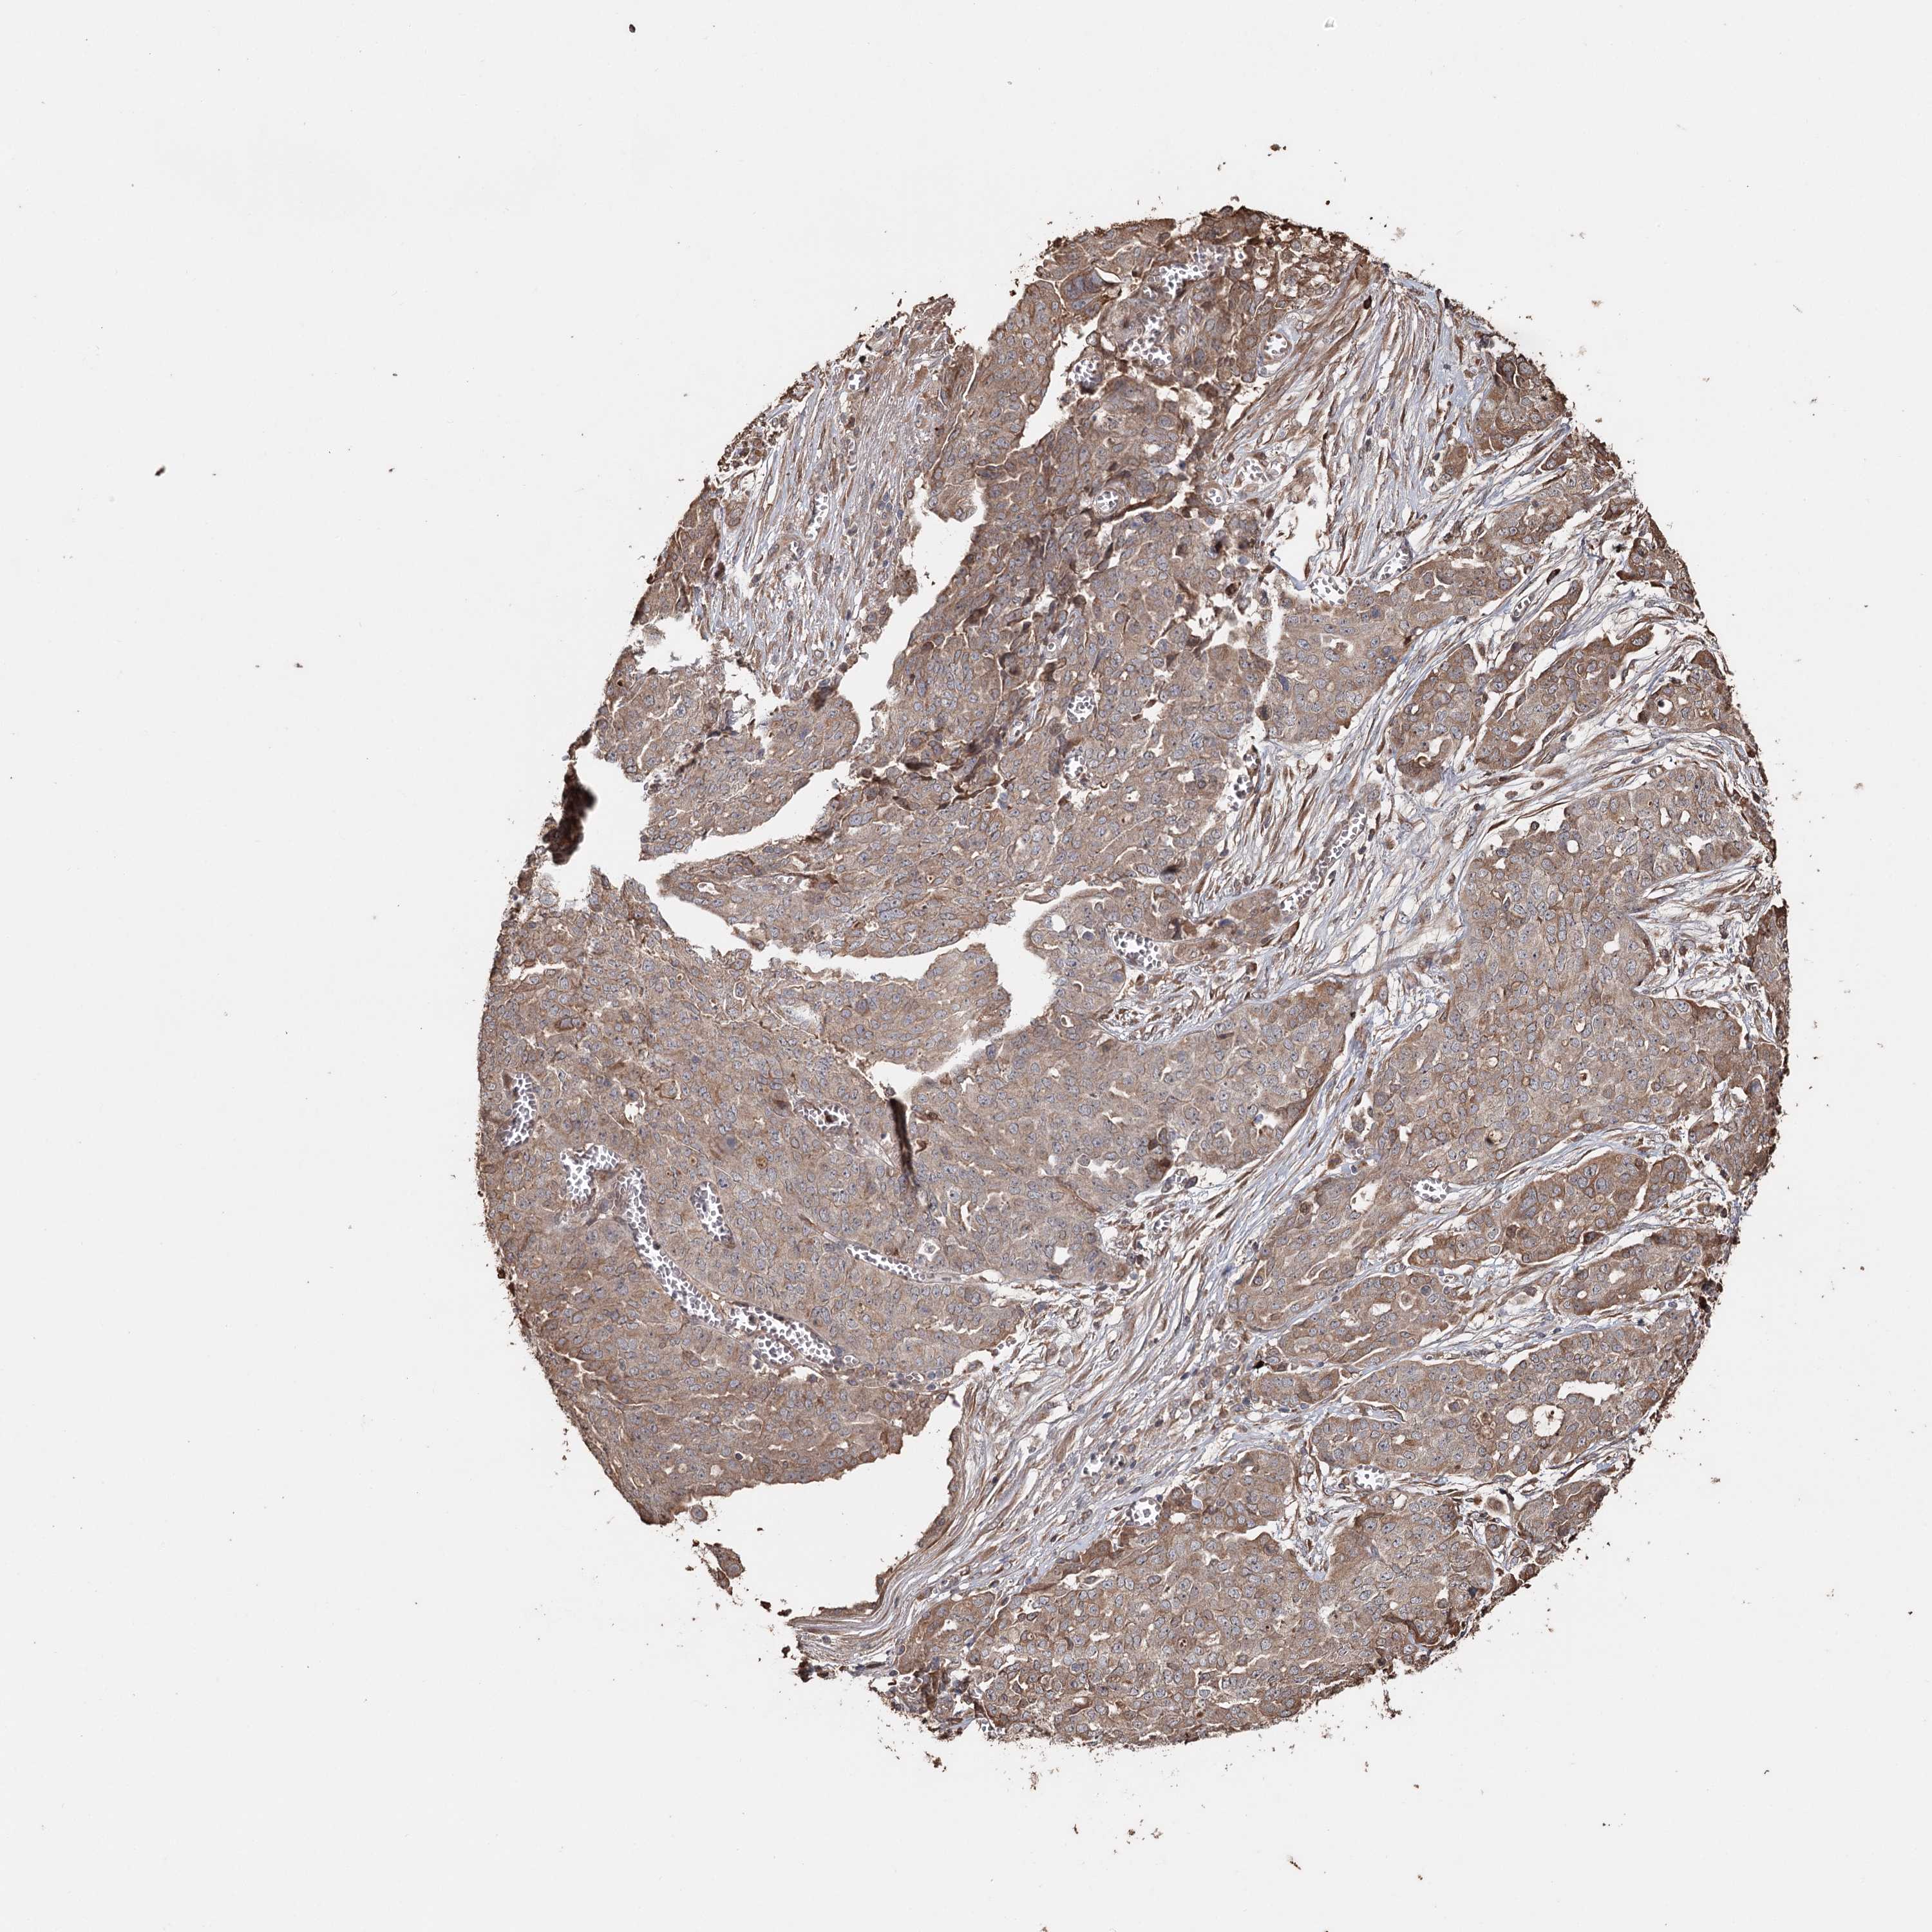

OVARIAN CANCER - Protein expressioni

A mouse-over function shows sample information and annotation data. Click on an image to view it in a full screen mode. Samples can be filtered based on level of antibody staining by selecting one or several of the following categories: high, medium, low and not detected. The assay and annotation is described here.

Note that samples used for immunohistochemistry by the Human Protein Atlas do not correspond to samples in the TCGA dataset.

Antibody stainingi

Antibody staining in the annotated cell types in the current human tissue is reported as not detected, low, medium, or high, based on conventional immunohistochemistry profiling in selected tissues. This score is based on the combination of the staining intensity and fraction of stained cells.

Each image is clickable and will lead to virtual microscopy that enables deeper exploration of all samples and also displays staining intensity scores, fraction scores and subcellular localization as well as patient and tissue information for each sample.

Antibody HPA005480

Antibody HPA024300

Antibody CAB037030

Cystadenocarcinoma, serous, NOS

Carcinoma, endometroid

Carcinoma, NOS

Cystadenocarcinoma, mucinous, NOS